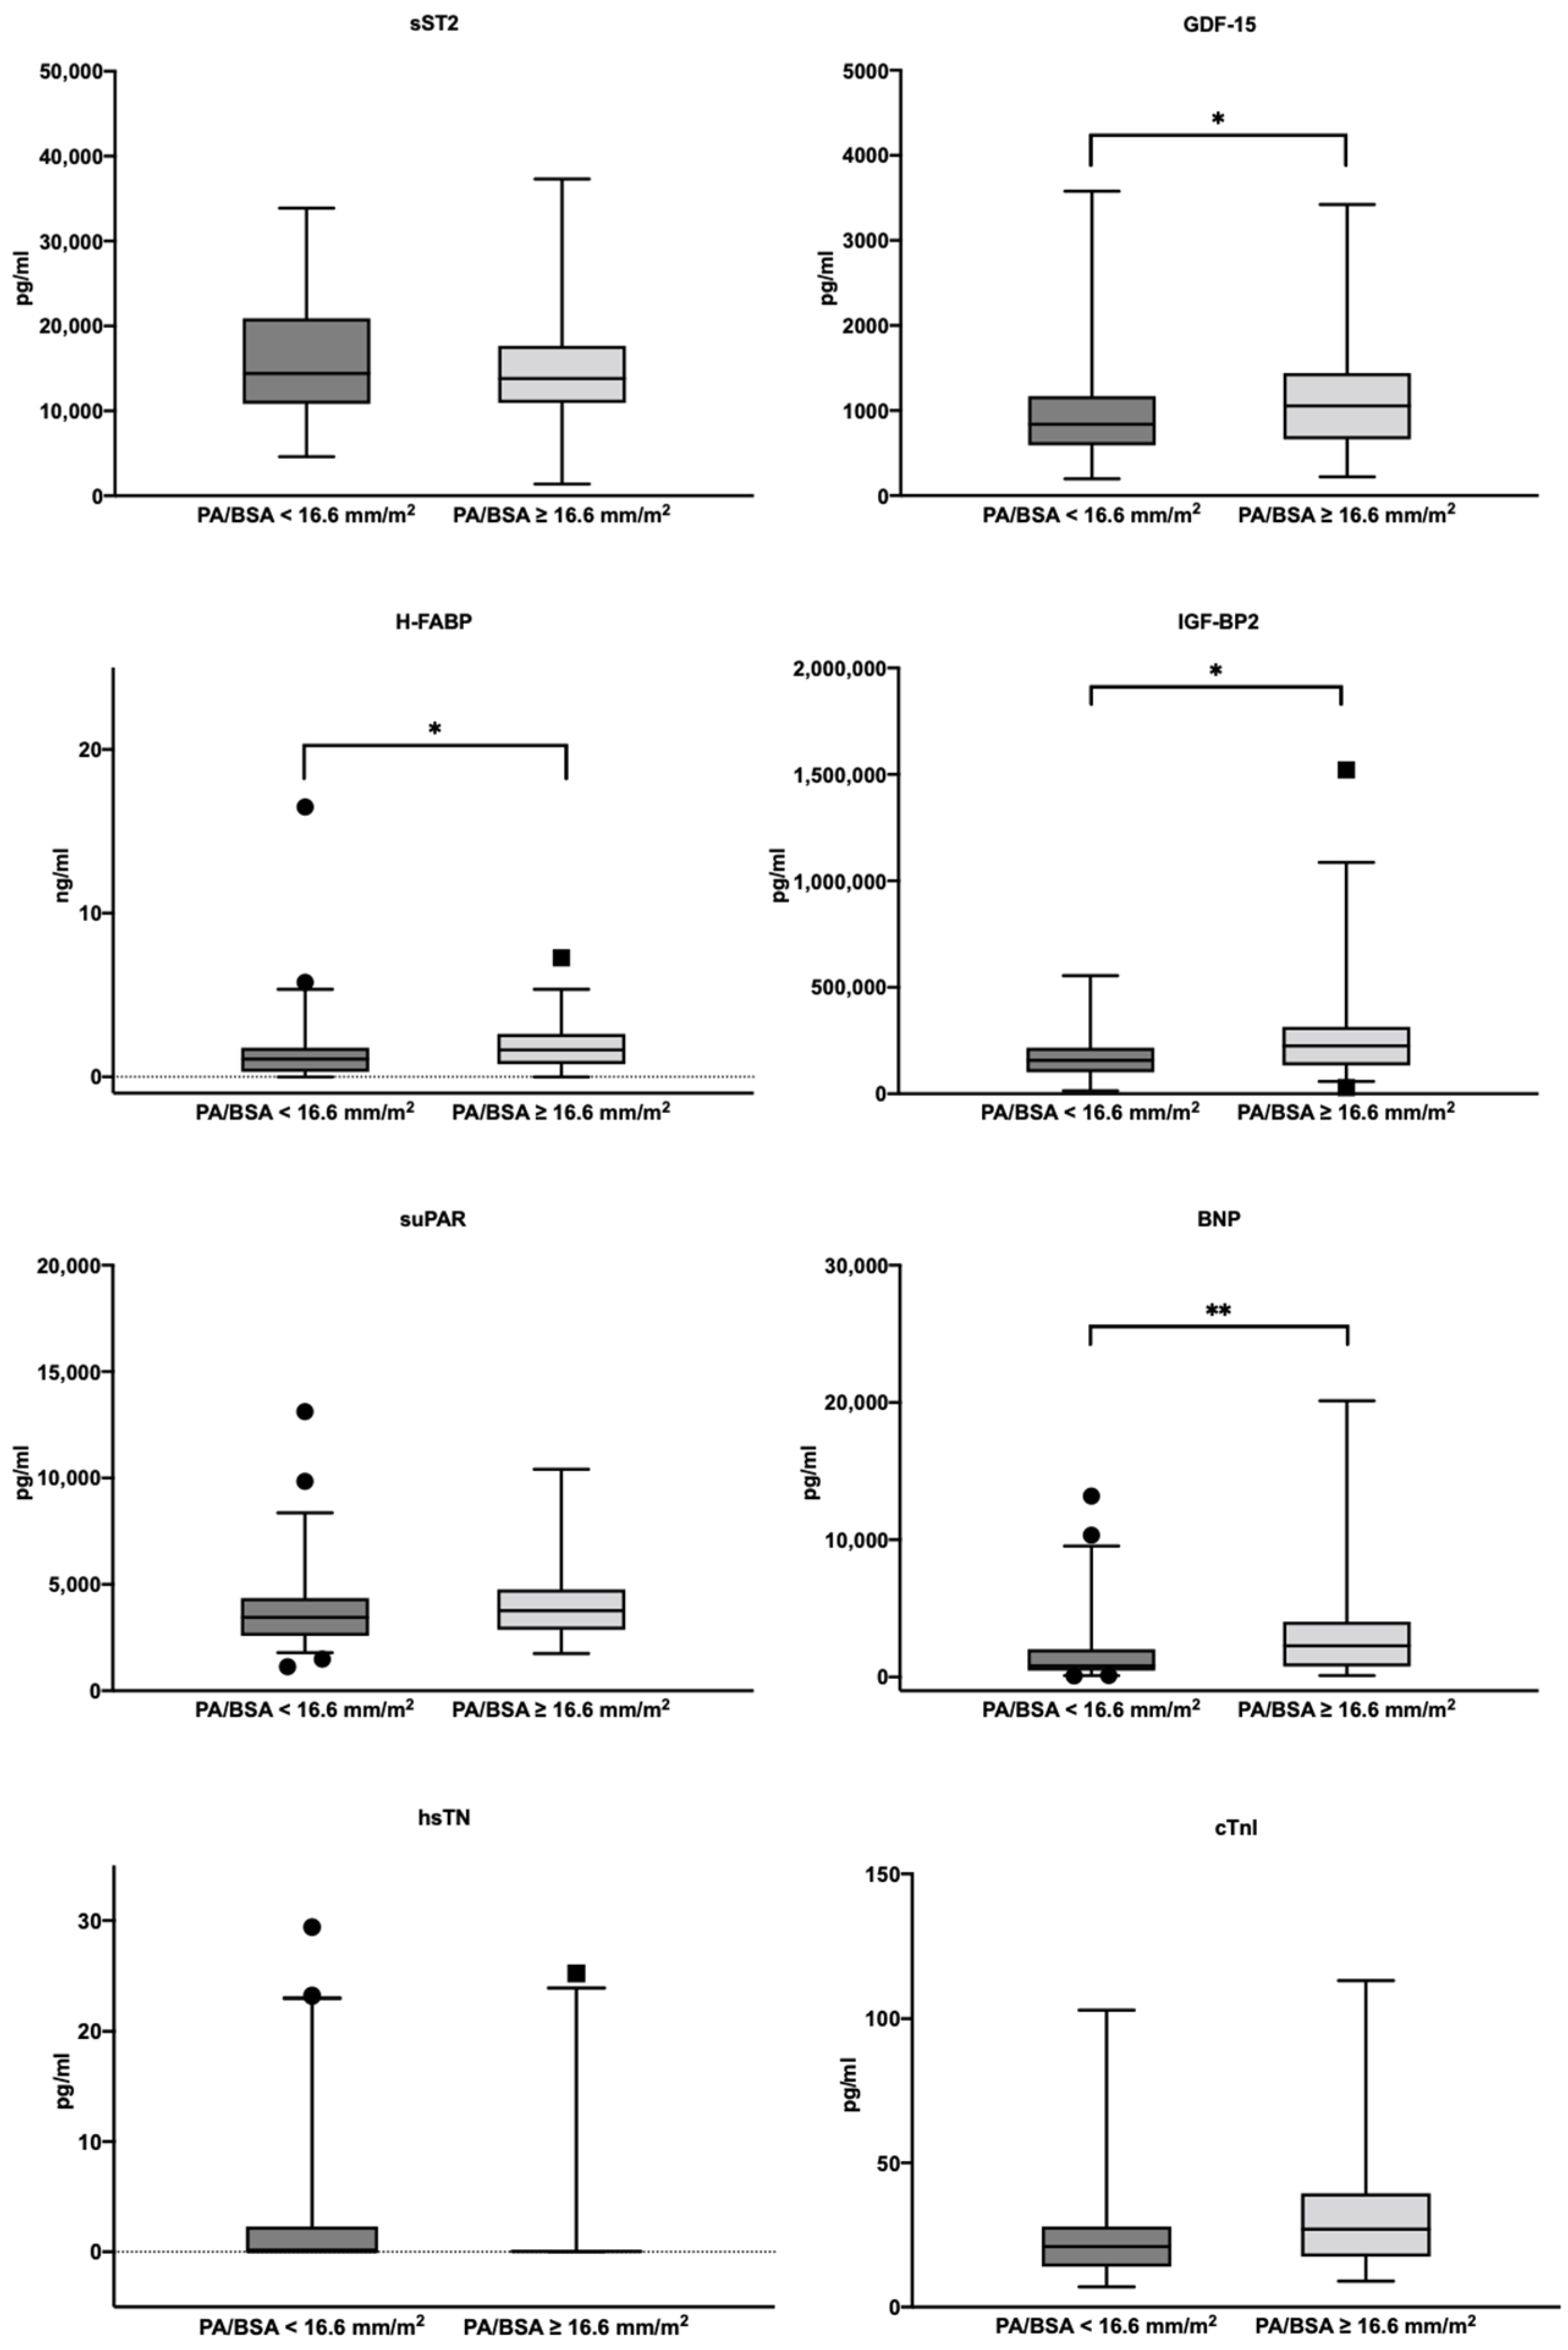

3.5. Biomarker Concentrations in the Study Cohort

3.6. AUROC Results—PA/BSA vs. Singular Biomarkers

4.3. Can a PA/BSA ≥ 16.6 mm/m2 Be Used Together with Biomarkers to Gain Additional Information?

| sST2 (pg/mL)—median ± IQR | 13,947.3 | 9073.6 | 14,399.6 | 10,086.8 | 13,806.6 | 6727.2 | 0.323 |

| GDF-15 (pg/mL)—median ± IQR | 922.8 | 707.5 | 840.1 | 577.7 | 1055.2 | 778.9 | 0.040 |

| H-FABP (ng/mL)—median ± IQR | 1.3 | 1.8 | 1.1 | 1.5 | 1.6 | 1.9 | 0.007 |

| IGF-BP2 (pg/mL)—median ± IQR | 178,153.7 | 134,892.6 | 156,947.6 | 115,637.5 | 225,232.1 | 180,916.1 | 0.005 |

| suPAR (pg/mL)—median ± IQR | 3524.1 | 1740.2 | 3449.2 | 1775.6 | 3767.5 | 1895.8 | 0.097 |